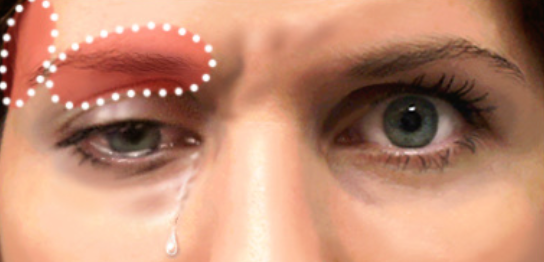

- Diagnosis: Cluster Headache

- Treatment: Oxygen mask - Triptans

- Prophylaxis: Lithium

20-year-old male. Severe headache, neck stiffness, photophobia & fever X 1 day. On examination, pain on extending the leg, as shown below:

20-year-old male. Severe headache, neck stiffness, photophobia & fever X 1 day. On examination, pain on extending the leg, as shown below:

Q1: What’s the clinical diagnosis? Meningitis

Q2: Name the 2 most common etiologic agents in this age group (names of bacteria)? Pneumococci, Meningococci

Q3: Which medicine will you give you close contacts of this pt for prophylaxis? Rifampicin | Ceftriaxone in pregnant